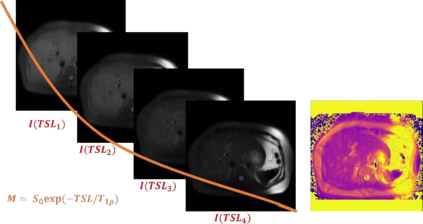

$T_{1\rho}$ mapping is a promising quantitative MRI technique for the non-invasive assessment of tissue properties. Learning-based approaches can map $T_{1\rho}$ from a reduced number of $T_{1\rho}$ weighted images, but requires significant amounts of high quality training data. Moreover, existing methods do not provide the confidence level of the $T_{1\rho}$ estimation. To address these problems, we proposed a self-supervised learning neural network that learns a $T_{1\rho}$ mapping using the relaxation constraint in the learning process. Epistemic uncertainty and aleatoric uncertainty are modelled for the $T_{1\rho}$ quantification network to provide a Bayesian confidence estimation of the $T_{1\rho}$ mapping. The uncertainty estimation can also regularize the model to prevent it from learning imperfect data. We conducted experiments on $T_{1\rho}$ data collected from 52 patients with non-alcoholic fatty liver disease. The results showed that our method outperformed the existing methods for $T_{1\rho}$ quantification of the liver using as few as two $T_{1\rho}$-weighted images. Our uncertainty estimation provided a feasible way of modelling the confidence of the self-supervised learning based $T_{1\rho}$ estimation, which is consistent with the reality in liver $T_{1\rho}$ imaging.